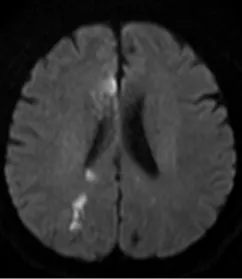

据了解,58岁的男性患者因“双膝关节麻木”入院,初诊时疑似腰椎相关问题。然而次日,患者出现感觉异常症状,经磁共振(MRI)检查确诊为双侧额顶叶多发新鲜脑梗死。医疗团队随即启动抗血小板、强化降脂等常规治疗,患者症状初步好转,但仅3天后病情便再次发作,复查MRI显示新增多处新发脑梗死,症状较前更为明显,常规治疗方案陷入瓶颈。

患者第一次就诊,双侧大脑半球多发脑梗死

患者再次就诊,出现了新的脑梗死病灶